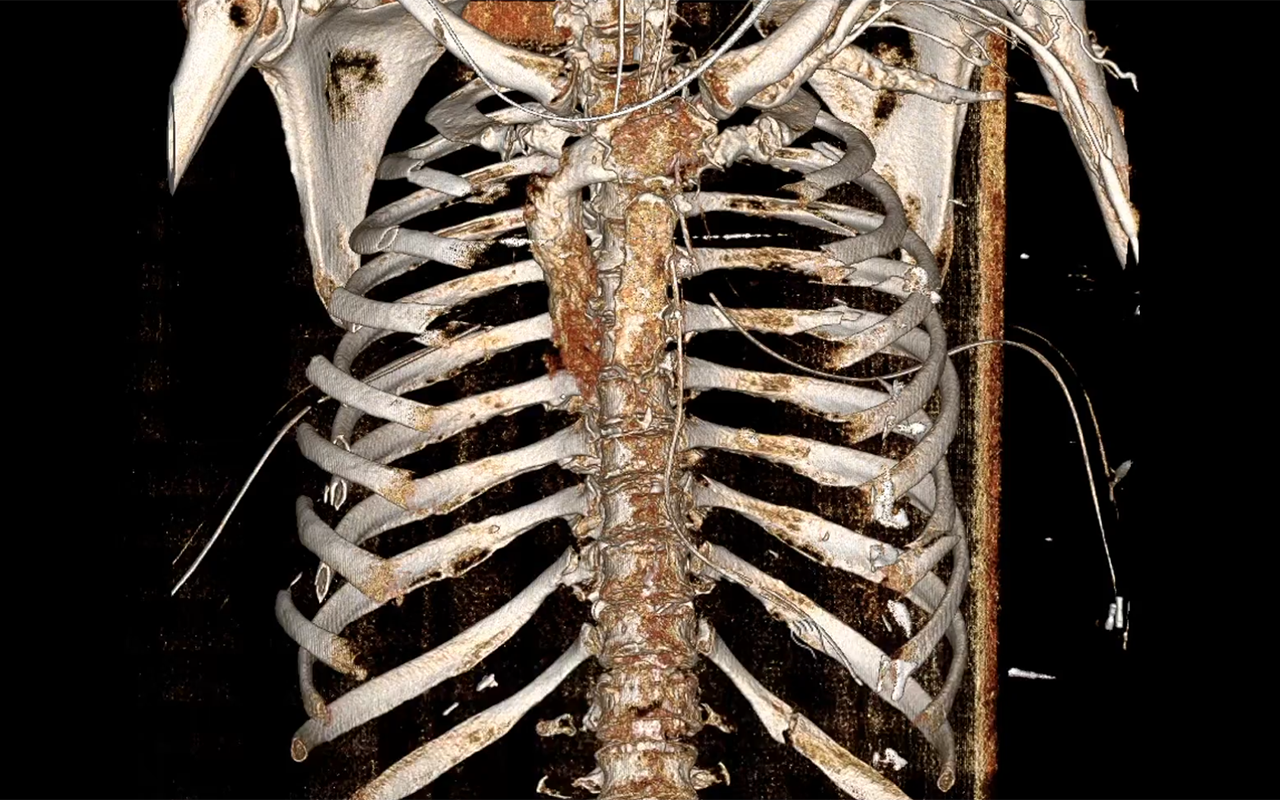

안전벨트 부서진 갈비뼈 EM_RESUS.png 미국의 응급 대응 의료진 샘 갈리(Sam Ghali) SNS에 올린 영상 갈무리 [사진 = 'EM_RESUS' X]

한 의학 전문가는 교통사고로 인해 심각한 부상을 입은 여성의 CT 스캔을 공개했다. 그녀의 갈비뼈는 여러 군데에서 부러졌고, 일부는 아예 원래 위치를 벗어나 자유롭게 떠다니고 있었다. 전문가들은 이러한 상태를 '동요흉' (Flail Chest)이라 부른다.

안전벨트 부서진 갈비뼈.png 미국의 응급 대응 의료진 샘 갈리(Sam Ghali) SNS에 올린 영상 갈무리 [사진 = 'EM_RESUS' X]